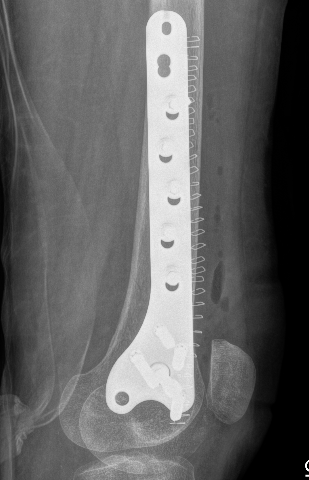

Management

Options

1. Medial plate + bone graft

2. Medial allograft cortical strut + bone graft

3. Distal femoral replacement

Revision medial plate + bone graft

Results

- cortical allograft strut with autograft and lateral plate

- addition of medial plate with autograft if lateral plate intact

- 16 nonunions

- all achieved union